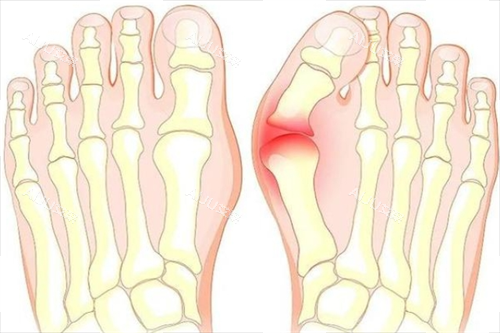

大脚骨,医学上称为拇外翻,是一种常见的足部畸形问题。

它不仅影响脚部的美观,还会导致疼痛、行走不便等问题,严峻影响患者的生活质量。